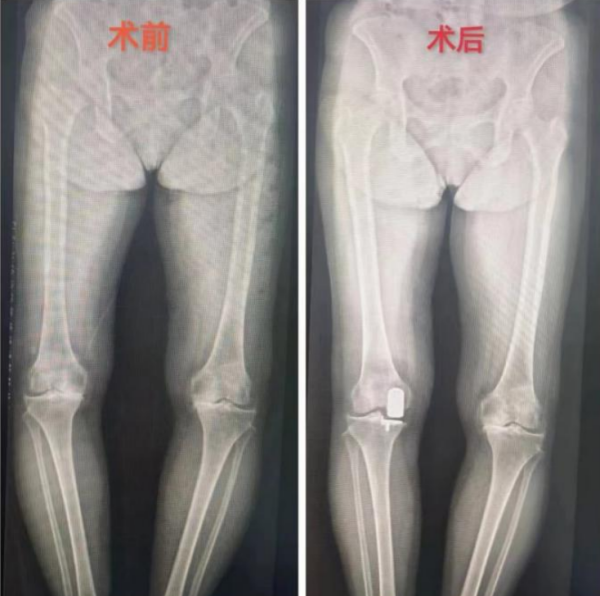

在临床案例展示部分,李良军深入讲解了来立博体育

运动医学科住院手术的老人。65岁的刘奶奶(化名),五年前确诊膝关节退行性病变,但没有接受治疗。一个月前,她的右膝关节疼痛开始异常剧烈,尤其在上下楼梯、爬坡或下蹲时加重,且活动受限明显,已经到了无法忍受的程度。在家人的陪同下,她前往运动医学科就诊。李良军阅片后,诊断刘奶奶的膝关节主要是内侧软骨磨损的特点,决定为她施行内侧单髁置换术。

李良军解释,单髁置换术相比全膝关节置换术,保留了患者没有磨损的软骨和正常的韧带,只置换了膝关节内侧或者外侧间隙磨损的那部分软骨,所以手术创伤更小、患者恢复更快,术后行动更加自如。本次手术十分成功,术后第二天,刘奶奶在病房走廊上自信地练习行走,并热情地与旁边充满好奇的病友分享自己经历,劝大家一定要早诊断早治疗。